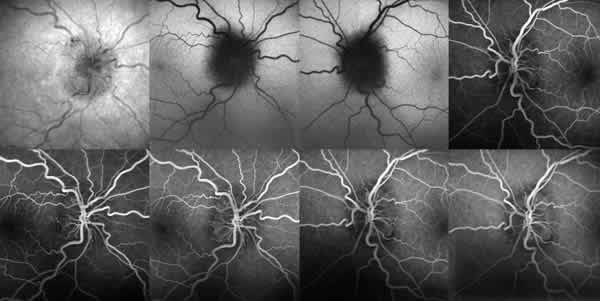

Se realizó una tomografía óptica de coherencia (OCT) cuyo resultado fue un aumento en el grosor de las fibras del rodete neurorretiniano. También se realizó una angiografía fluoresceínica (AFG) en la que no se observaron fugas (fig. 2).

Fig. 2: Angiografía con fluoresceína. Caso n.º 1, en OD no se

observan fugas ni otras alteraciones. En OI tampoco se observan fugas ni otras

alteraciones.

Fig. 5: Caso n.º 2, en la AFG se observa fuga de contraste en

ambos ojos.